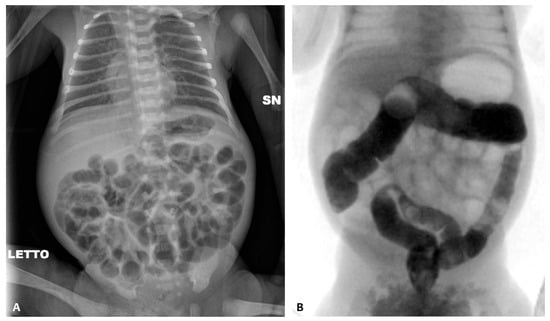

A second episode of intestinal sub-occlusion occurred, with diffuse dilated intestinal loops at the abdomen X-ray (Figure 6). NAC rectal enemas were given. Because of the lack of clinical improvement, a barium enema was performed, documenting a dolichosigma, with a regular caliber of the whole colon and without caliber changes, and a medialized cecum and colon in relation to the marked distension of the small bowel, with an overall picture of intestinal malrotation. Cystic fibrosis was ruled out via genetic sequencing and a sweat test.

An ileostomy was performed at 10 cm from the ileocecal valve, with the resolution of obstructive symptoms and enteral tolerance. The stoma was closed after 2 months. He was discharged home at the corrected age of around 3 months.

Figure 6. Abdominal X-ray of patient P6 at 34 weeks of postmenstrual age at our NICU admission (A) and after NAC rectal enemas (B); barium enema documenting dolichosigma and intestinal malrotation (C); and abdominal X-ray at discharge (D).